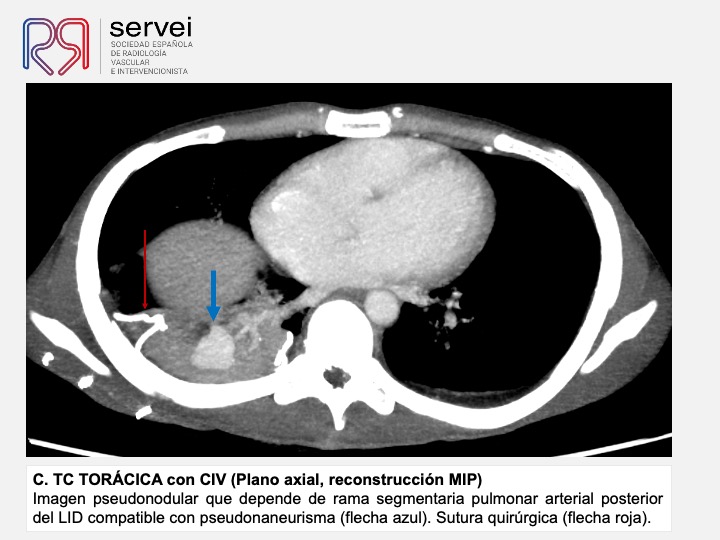

- Pseudoaneurisma pulnonar herida arma fuego 01

- Pseudoaneurisma pulnonar herida arma fuego 02

- Pseudoaneurisma pulnonar herida arma fuego 03

- Pseudoaneurisma pulnonar herida arma fuego 04

- Pseudoaneurisma pulnonar herida arma fuego 05

- Pseudoaneurisma pulnonar herida arma fuego 06

- Pseudoaneurisma pulnonar herida arma fuego 07

- Pseudoaneurisma pulnonar herida arma fuego 08

- Pseudoaneurisma pulnonar herida arma fuego 09

- Pseudoaneurisma pulnonar herida arma fuego 10

- Pseudoaneurisma pulnonar herida arma fuego 11

- Pseudoaneurisma pulnonar herida arma fuego 12